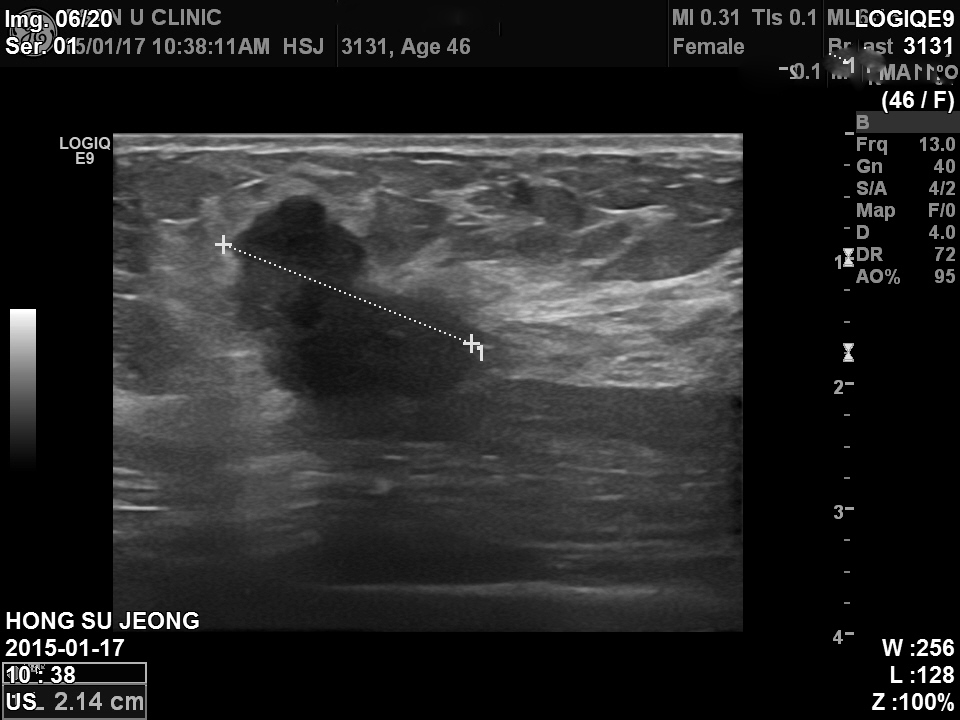

건강검진상 이상소견으로 내원한 만 46세 여성분입니다.

좌측 유방 상외측, 겨드랑이 근처에 2cm 이 넘는 혹이 있었고

그외에도 여러개의 혹들이 있었지만, 다 악성의심소견은 없어

위 사진의 혹만 조직검사하여

침윤성 아포크라인암이 진단되었읍니다.

다행이 같은쪽 겨드랑이에는 전이의심소견이 없습니다.